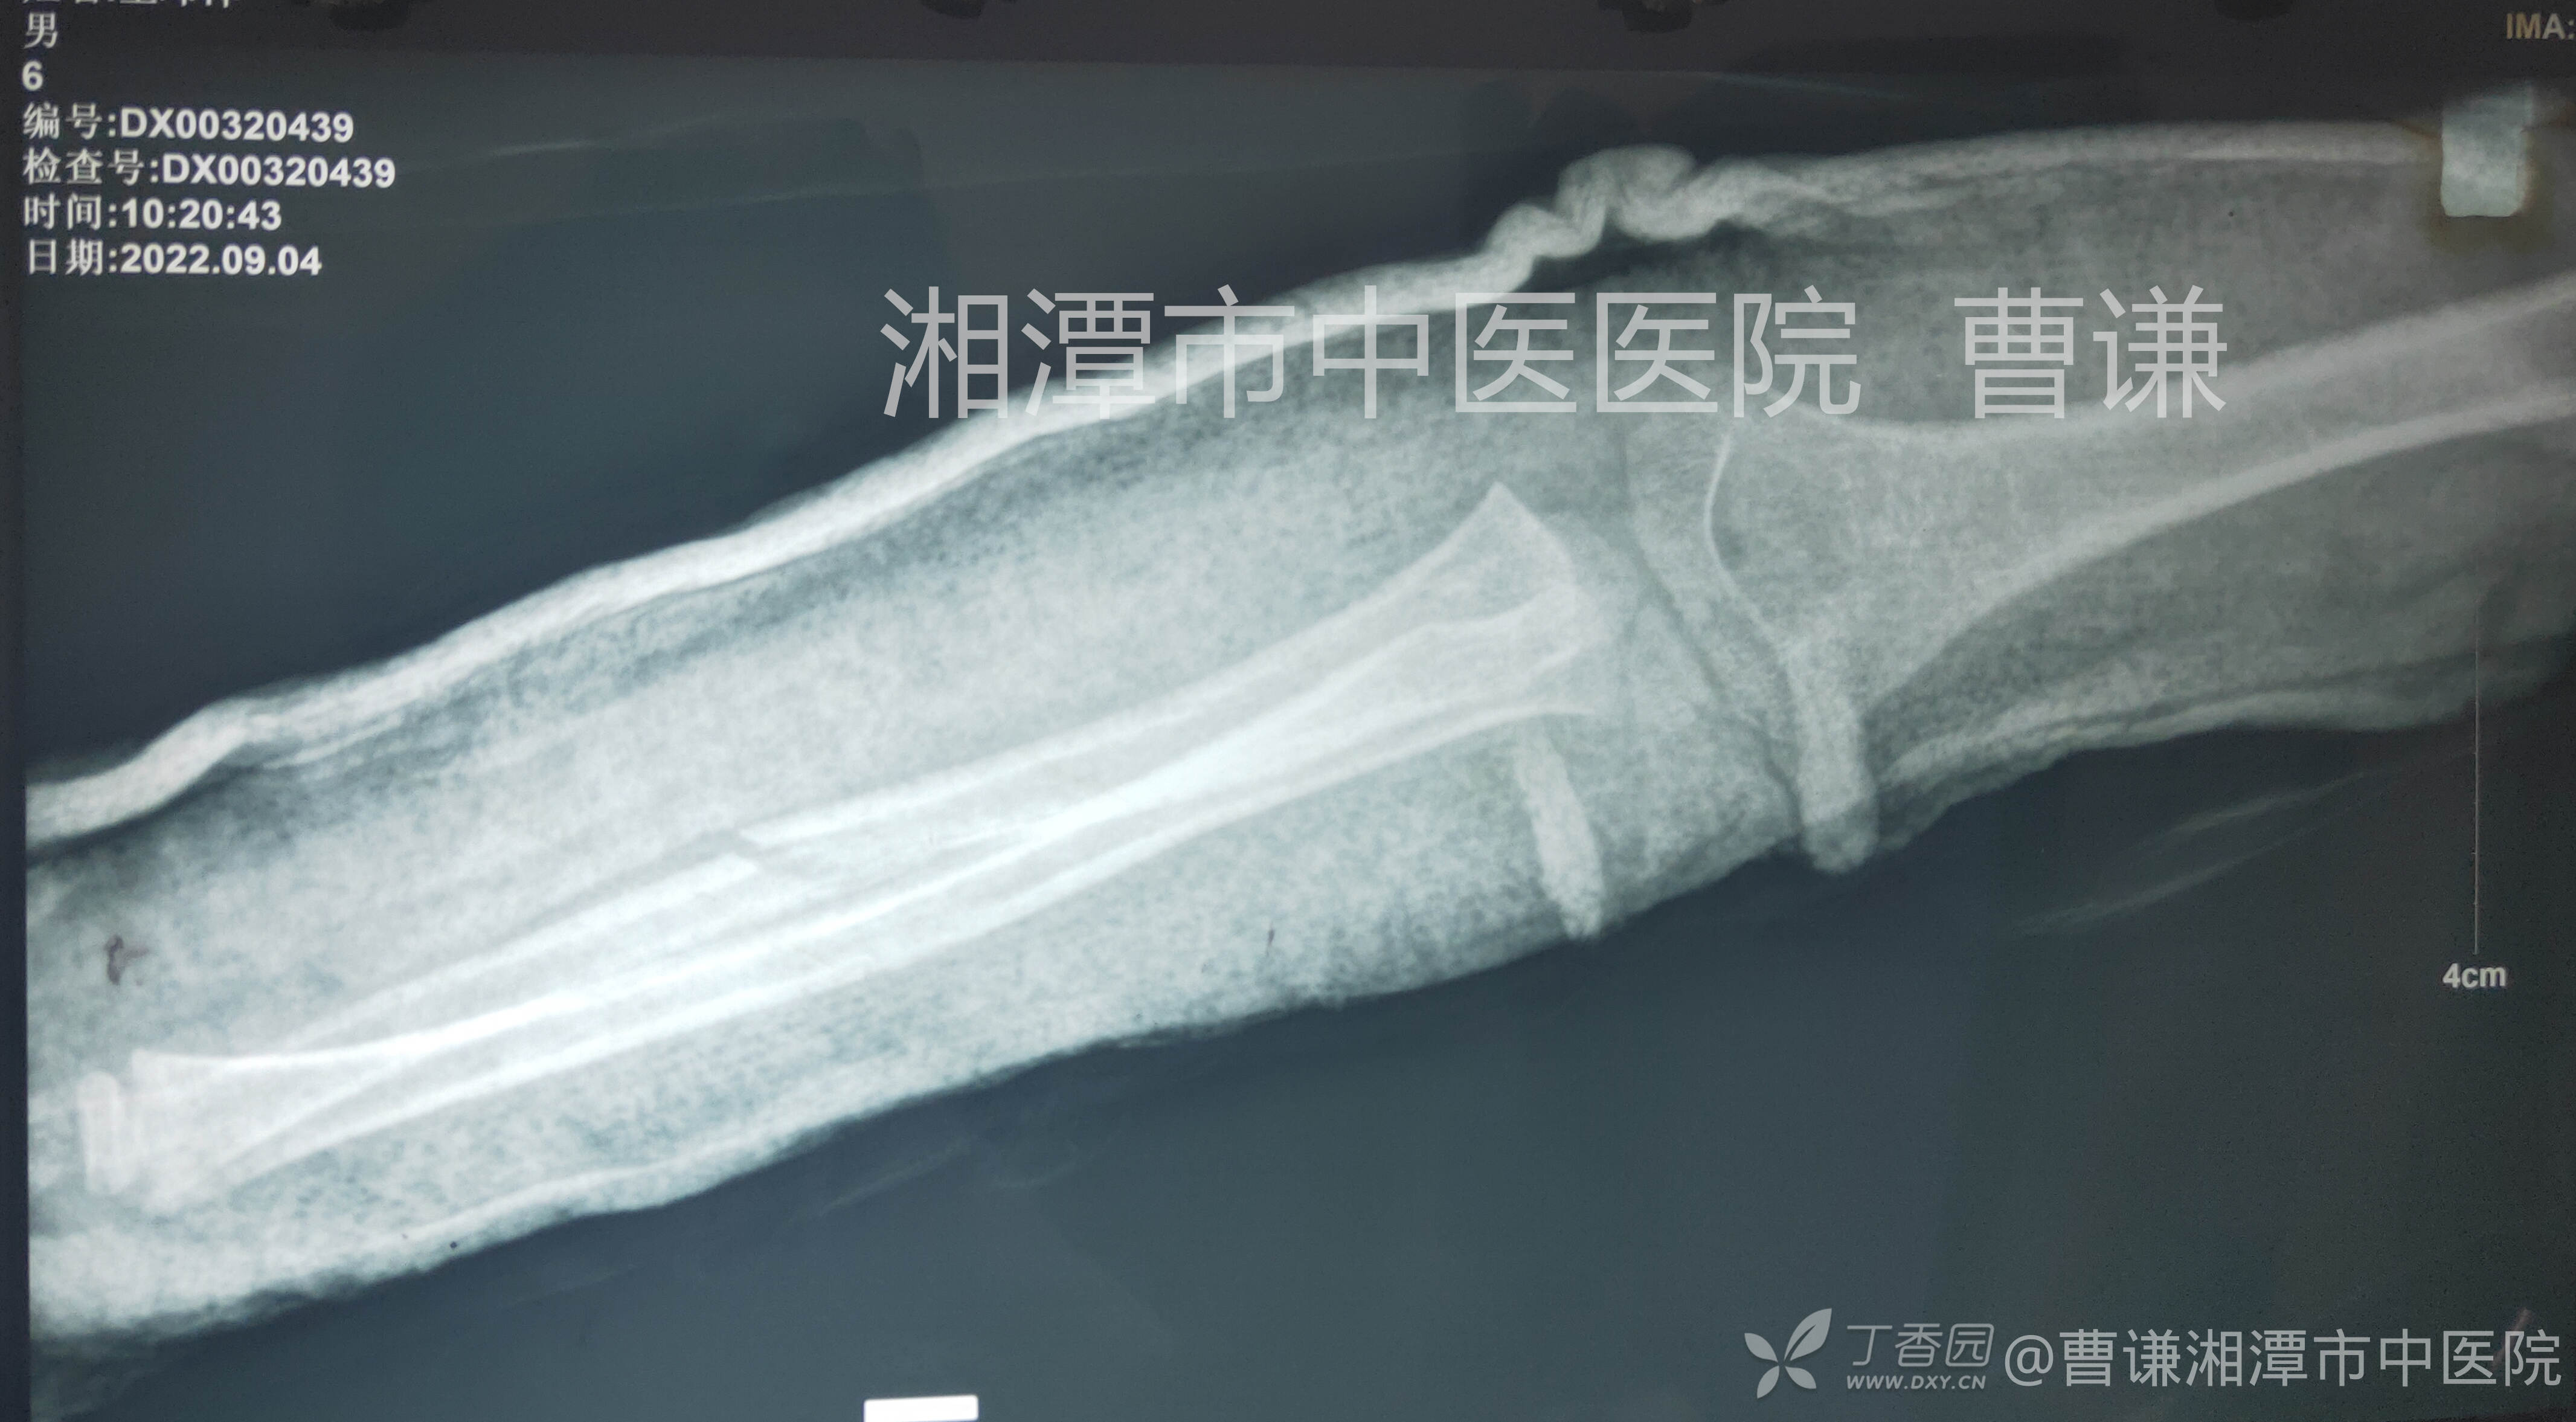

伤后12天复查,肘关节拍摄不全,前臂也并非标准体位拍摄,肱桡关系无法正确评价。

伤后14天又就诊于衡山县骨伤科医院,拍片复查示桡骨头仍脱位。建议患者行手术治疗,患者家属拒绝手术治疗。转而就诊于我院要求保守治疗。